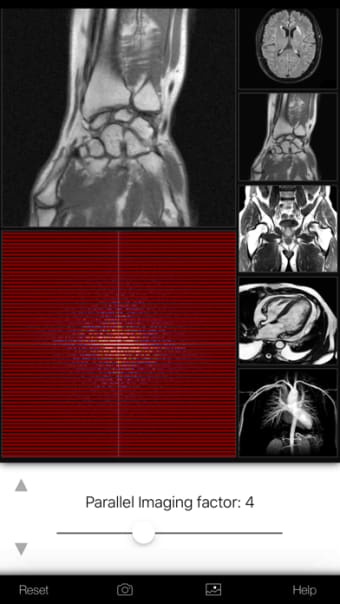

Een volledige versie app voor iPhone, door Eltjo Haselhoff.

A K-Space Odysseyis een app met volledige versie voor iPhone, die deel uitmaakt van de categorie ' Geneeskunde'.

Over A K-Space Odyssey voor iPhone

Een K-Space Odyssey is beschikbaar voor iOS 12.1.2 of hoger. De huidige versie van de software is 1.9.1 en u kunt deze alleen in het Engels krijgen.